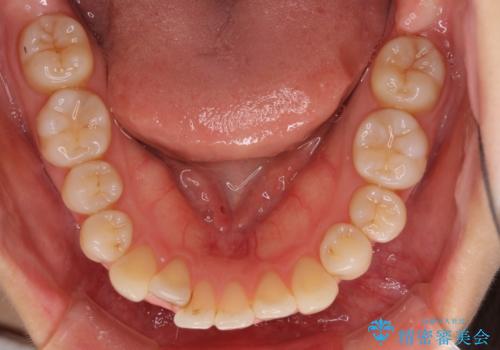

- 上下前歯のデコボコを気にして来院された患者様です。

インビザラインによる上下歯列の側方拡大と後方移動、IPR(歯と歯の間を削る)にるスペースの獲得により歯列を整えることとしました。